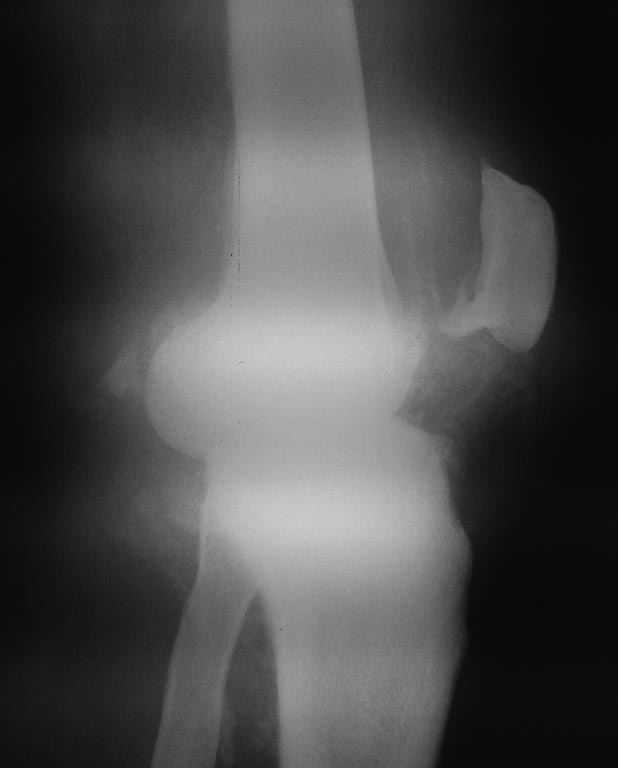

Постсифилитическая артропатия |

Коллеги, поделитесь опытом, пожалуйста, в методах лечения сустава Шарко правого коленного сустава, заранее благодарен.

If a neuropathic knee is painless, bracing is the treatment of choice; however, many patients have disabling pain, and operative treatment should be considered for these patients. Controversy still surrounds the inclusion of neuropathic arthritis as an indication for total knee arthroplasty. Several authors reported success with constrained and semiconstrained prostheses in neuropathic arthropathy, but the number of patients has not been large, and the length of follow-up has been short. Hui and Fitzgerald reported generally good results in five knees with neuropathic arthritis at an average of 3.3 years after hinged total knee arthroplasty. Matthews and Kaufer performed seven spherocentric total knee arthroplasties in four patients with clinical or radiographic evidence of neuropathic arthropathy. Within an average of 4 years, aseptic loosening developed in one patient, and instability developed in another. Soudry et al. reported good results at an average 3 years after surgery in nine knees with Charcot and Charcot-like joints using posterior stabilized condylar-type prostheses, most of which were custom-made to compensate for femoral or tibial bone deficits. Many authors have reported failure of total knee arthroplasty in patients with neuropathic arthropathy, most of which occurred with unconstrained prostheses. Kim, Kim, and Oh reported that at 5-year follow-up only 10 (53%) of 19 total knee arthroplasties in patients with Charcot arthropathy were satisfactory; serious complications were frequent. Parvizi, Marrs, and Morrey reported improvements in pain and function at 7 years after 40 total knee arthroplasties in 29 patients with Charcot joints; however, methods usually reserved for complex revision total knee arthroplasty were required in most of the procedures. Our limited experience with total knee arthroplasty in neuropathic knee joints also has been disappointing.

Although sometimes difficult to achieve, arthrodesis is considered the treatment of choice for painful neuropathic arthritis of the knee. Techniques of arthrodesis are described in Chapter 3, but some general principles should be kept in mind for patients with neuropathic knee joints, as follows: (1) complete débridement of all hypertrophic synovium, (2) careful carpentry of apposing bone surfaces, (3) strong internal fixation, and (4) adequate external support after arthrodesis